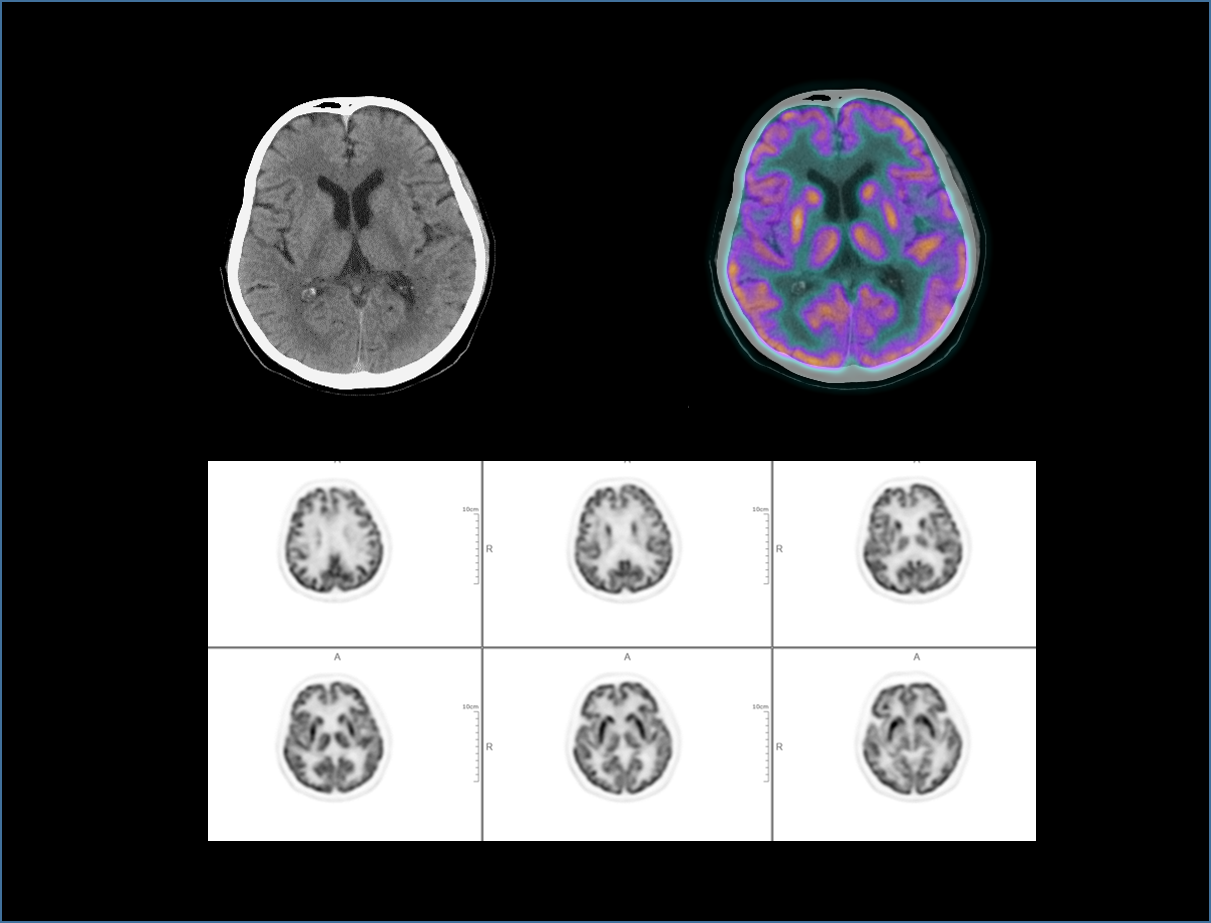

With the unique Integrated-Light-Guide Digital PET technology and a 160-slice CT system, uMI Vista combines high quality functional images with fine anatomical structure visualization. The state-of-the-art reconstruction technology and comprehensive applications further boost diagnostic precision in oncology, neurology and cardiology.

Clarity Imaging Chain

2.9mm NEMA Resolution

Outstanding resolution performance is achieved through systematic imaging chain engineering.

HYPER Iterative Reconstruction

Improves signal-to-noise ratio and contrast recovery to aid lesion detectability and quantitative accuracy.